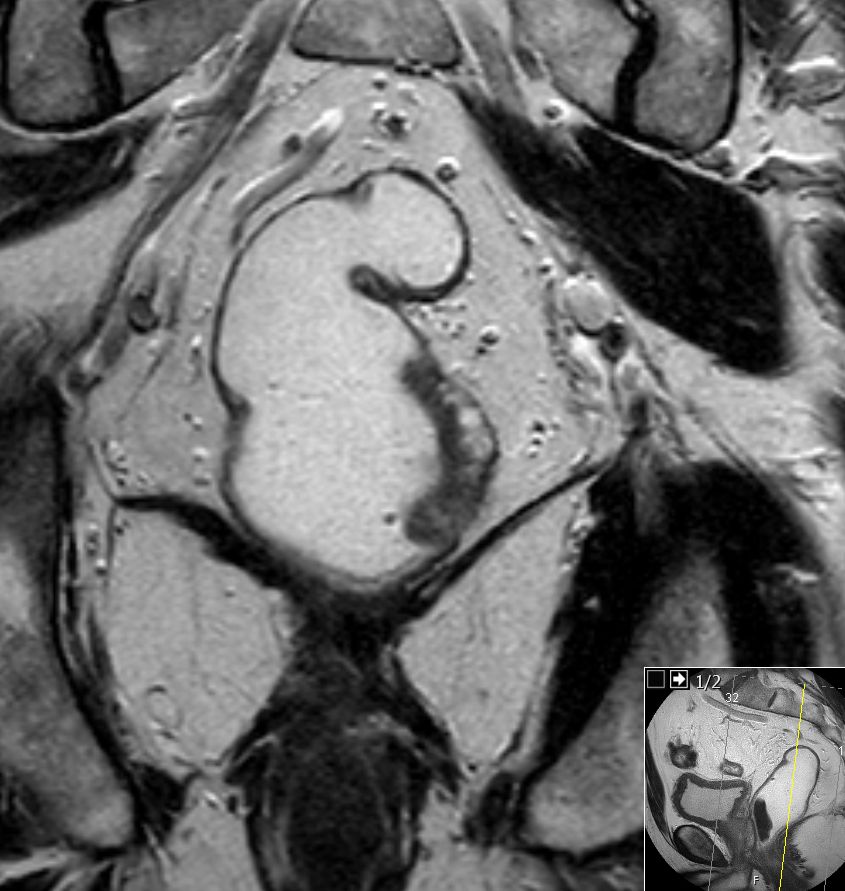

| MRT: T2 | 69-jähriger Mann mit mäßig differenziertem

Adenokarzinom bei 15 cm.![]() |

![]() |

![]() | |